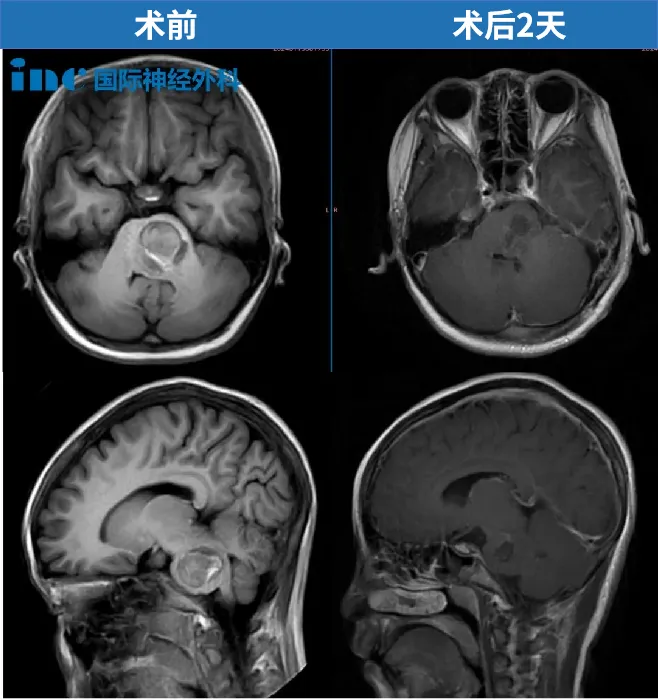

2岁,聪聪,脑干-脑桥海绵状血管瘤,2019年巴教授中国示范手术,顺利全切肿瘤,目前已经在上幼儿园。

3岁,浩浩,脑干胶质瘤,体重只有16kg,对手术和出血的耐受力极差。2024年巴教授中国疑难示范手术,于北京天坛医院成功示范手术。

6岁,琦琦,脑干延髓,一直延伸至颈5节段脊髓,2019年巴教授中国示范手术,肿瘤几近全切。术后3年,琦琦可以像正常孩子一样玩耍。

11岁,贝贝,脑干海绵状血管瘤出血,120急救送进ICU、病情危急,2024年巴教授为其成功示范手术,目前已回归校园。

12岁,小宇,脑干海绵状血管瘤伴出血,2022年巴教授中国疑难示范手术,顺利全切,目前在读小学。

33岁,郑女士,15cm肿瘤起源于脑干下部,累及延髓和颅颈交界区,且向下方延伸到整个颈部脊髓以及一直到第一胸椎水平。2022年巴教授中国疑难示范手术,顺利近全切。

中脑胶质瘤手术案例

脑桥胶质瘤手术案例

延髓胶质瘤手术案例